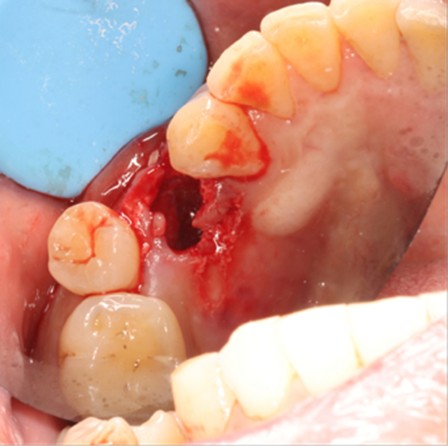

May 4, 2025: Extraction of the affected tooth.

Immediate implant placement (first-stage surgery) was performed right after tooth extraction.

Postoperative CT scans and intraoral photographs were obtained.